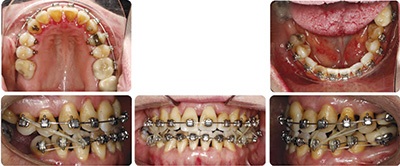

Diagnosing from “outside-in,” she showed lower 1/3 vertical facial height in slight excess, a prominent chin and mild mandibular asymmetry to the right. Unfavorable dark triangles are obvious in her smile because of periodontal recession. She shows only mild Class III occlusion, but a significant number of teeth are in full crossbite position. Notable cephalometric findings include mild mandibular prognathism, a high mandibular plane angle and lower incisors that are slightly compensated/upright as you might expect with a Class III excess mandible. Multiple areas of varying bone loss are present and the LR8 was given a poor long-term prognosis by the dentist.

Orthognathic surgery was discussed with Shelley as the most ideal plan, with a lesser risk of periodontal stress compared to the non-surgical plan, but Shelley declined that ideal option. When I had Shelley open slightly, I could see that her lower jaw dropped down and back enough to bring her into an edge-to-edge bite with the upper left central incisor. I knew that if I could disclude her properly, unravel the upper crowding and close the minimal space on the lower, her occlusion should fall very close to where we would need it. The big decision in this case was where and how to disclude her.

I felt that choosing to place the bite turbos on posterior teeth would be unfavorable for two reasons. First, posterior turbos tend to limit posterior extrusion and overall vertical opening. Posterior extrusion and vertical opening of the MPA alone favor occlusal correction of Class III to Class I and underbite correction as the lower jaw rolls slightly down and back. Second, in Shelley’s case, if the posterior teeth were intruded at all, great care would be needed at the end of treatment to make sure that these teeth completely settled into full contact to prevent a harder than ideal occlusion on the anterior teeth (the lower incisors show significant periodontal loss).

I also felt that placing the bite turbos on the incisors, perhaps in a Class III ramp bonded to all the lower incisors, would also not be as ideal in her case. While a Class III ramp is an excellent choice for mild Class III patients with an underbite, Shelley has compromised support for her lower incisors, and I would not choose to concentrate the force of her bite on those teeth.

Instead, the turbos were placed on the lower canines and first bicuspids. These teeth, and the maxillary canines that would abut them, showed relatively good periodontal support and longer roots. They could likely shoulder the concentrated masticatory load in this periodontally compromised patient for more than a few months of treatment if needed. Also the turbos were shaped into a ramp (they sloped in to the lingual) to give function to their form. As the maxillary canines (which were in crossbite) hit the ramps, there would be a labial crown-tipping effect to jump their position out of crossbite as the maxillary teeth aligned. Crossbite elastics also played an important role in this regard as well.